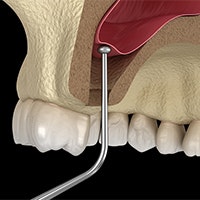

Treating Disease & Infection During Full Mouth Reconstruction

Gum Graft

Gum recession leads to lost tissue that can make you more susceptible to periodontal disease and tooth decay. We can surgically transfer tissue into these areas to restore your gumline with a gum graft.

Scaling & Root Planing

We can treat gum disease with scaling and root planing, a deep cleaning performed below the gumline. This plaque-eliminating procedure can protect your health and make you a suitable candidate for additional restorative services.

Root Canal Therapy

Advanced tooth decay can become an outright infection. This endangers the tooth and can cause major pain and other health risks. We can remove diseased tooth pulp with root canal therapy before providing your full mouth reconstruction.